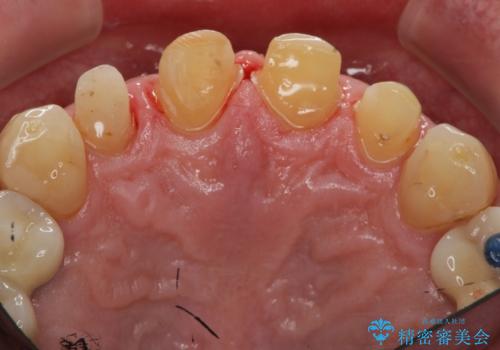

「 放置した虫歯 」 前歯セラミック治療

- 前歯の虫歯に気付きながらも放置し、一念発起し治療を希望され来院されました。

虫歯のマイクロスコープによる丁寧な除去、根管治療、深い虫歯に対する挺出(エクストリュージョン)および歯周外科を行ったのち精度の高いセラミッククラウン製作治療を計画します。

虫歯の放置により、根管治療や深い虫歯に対する処置が必要になりましたが丁寧に一つづつ処置を行ったことで抜歯をすることなく歯を残すことができました。

セラミッククラウンの製作をする前に、歯内・歯周環境の整備は非常に大切です。